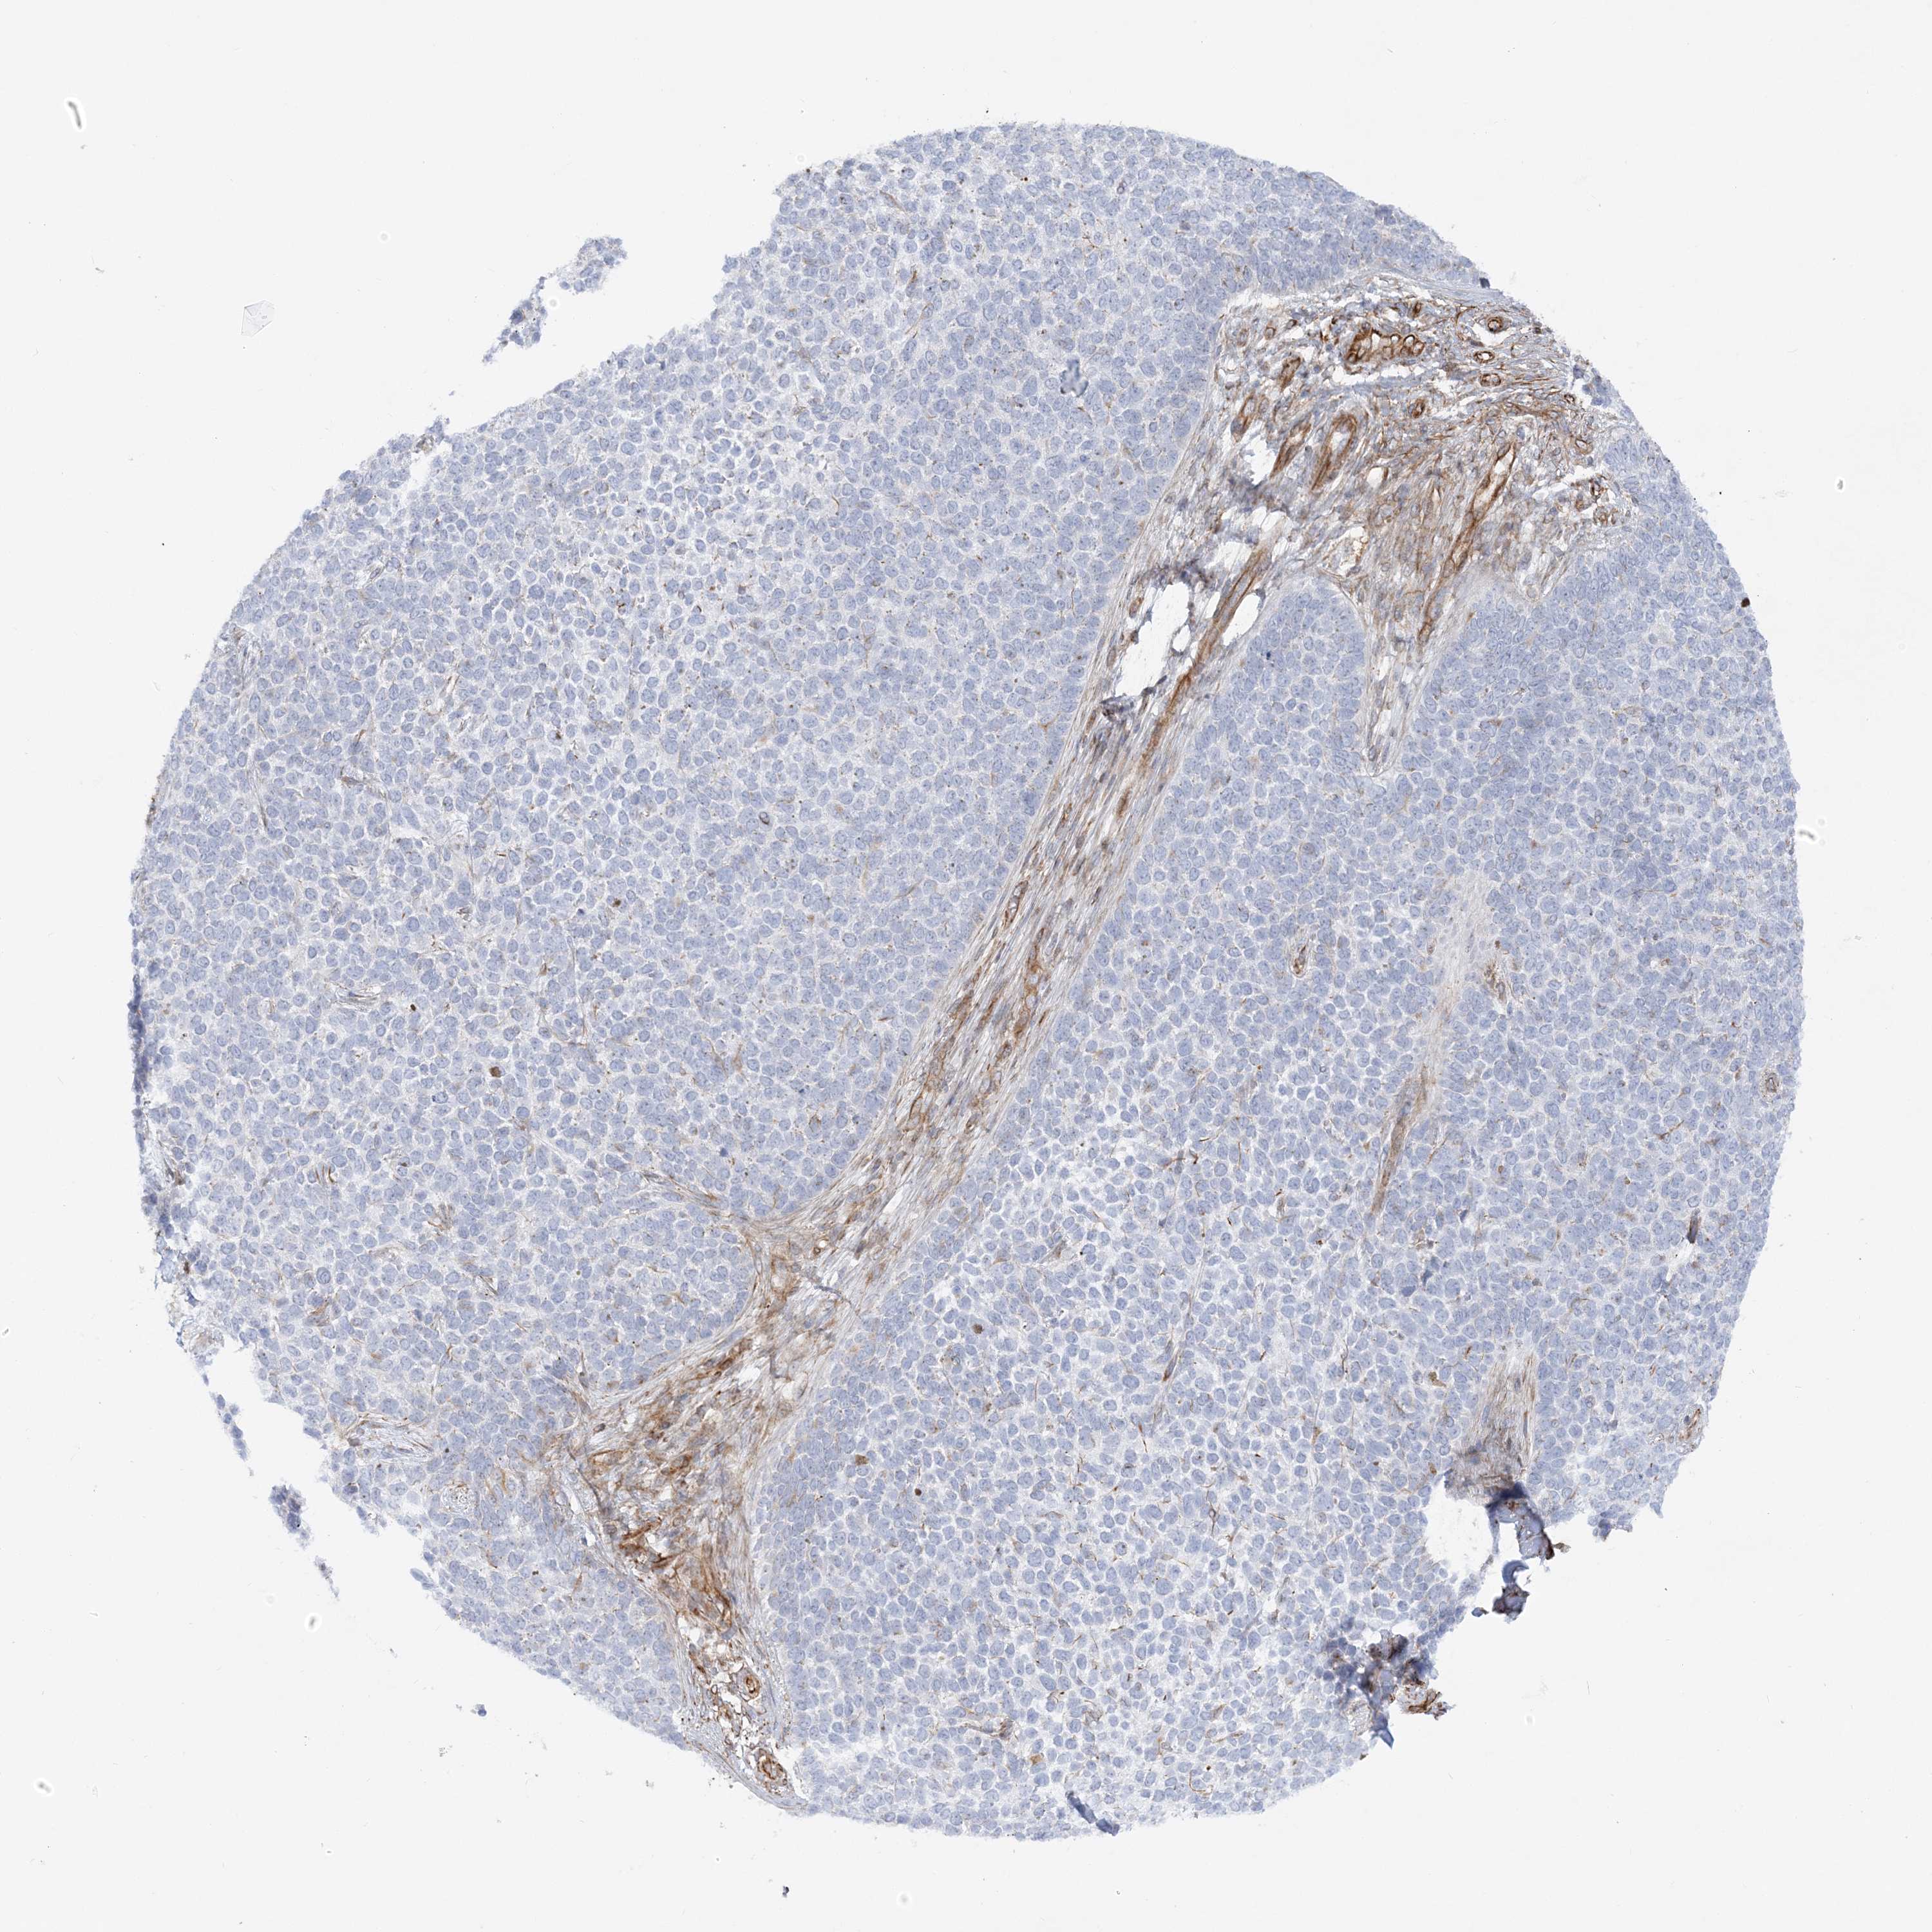

Basal cell and squamous cell cancer

SKIN CANCER - Protein expressioni

A mouse-over function shows sample information and annotation data. Click on an image to view it in a full screen mode. Samples can be filtered based on level of antibody staining by selecting one or several of the following categories: high, medium, low and not detected. The assay and annotation is described here.

Each image is clickable and will lead to virtual microscopy that enables deeper exploration of all samples and also displays staining intensity scores, fraction scores and subcellular localization as well as patient and tissue information for each sample.

Antibody HPA036560

Antibody HPA036561

Squamous cell carcinoma, NOS